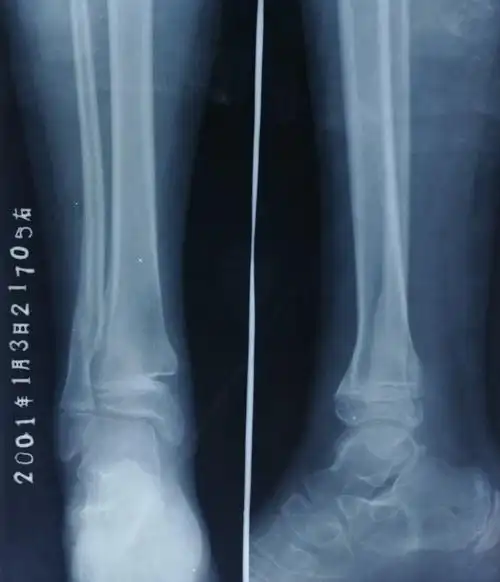

病例一,11岁,男孩,桡骨远端骨折,背侧移位.

小儿桡骨远端青枝骨折